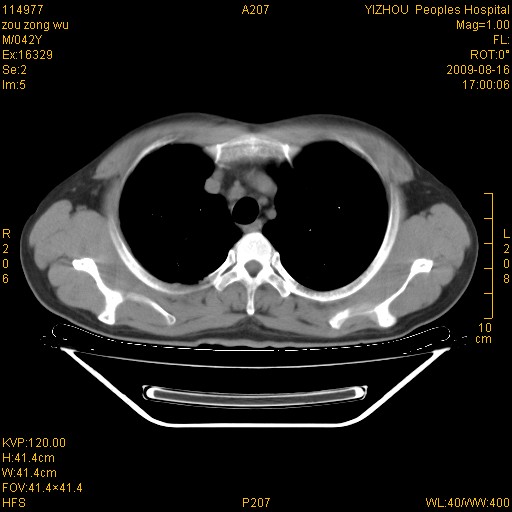

以下是引用zjzjr在2009-8-17 10:42:00的发言:[br]右侧间质性肺炎伴纤维化,右肺下叶肺囊肿伴感染(不除外外伤后引起),右肺野及胸壁软组织\\肝内见多发斑点状,中枪了吧.右侧胸膜肥厚\\粘连.